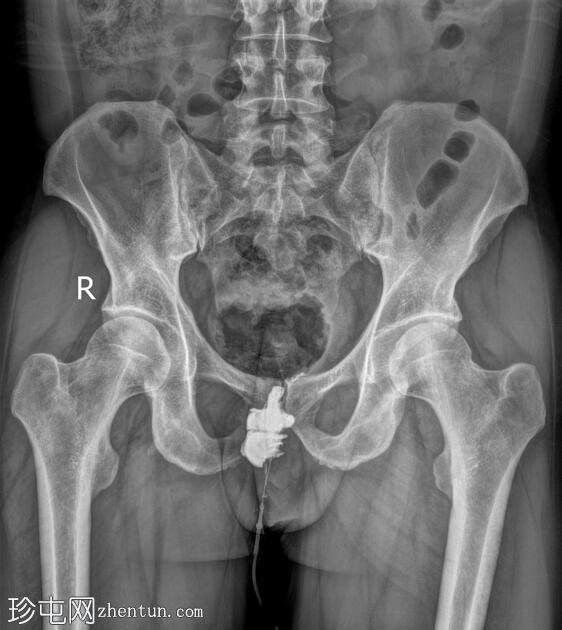

正位

经脓性分泌物开口注入造影剂,显示右侧肛周脓肿显影。

未见造影剂明显外渗至肛管或直肠。

透视瘘管造影图像显示右侧肛周脓肿较大,与肛管或直肠无交通。